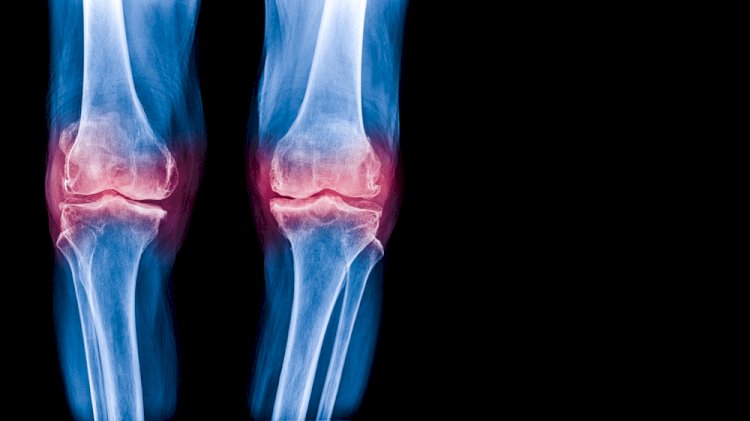

You might be wondering, “How do doctors tell the difference?” Diagnosis usually starts with a conversation about your symptoms and a physical exam. If you’re having joint pain, your doctor may order X-rays or MRI scans.

• For sclerosis, Doctors look for areas where the bone appears denser or whiter than normal on X-rays. This is often seen under the cartilage in joints.

• For osteoarthritis, X-rays might show joint space narrowing, bone spurs, and sometimes sclerosis as well. Doctors also consider your symptoms, like pain, stiffness, and swelling.